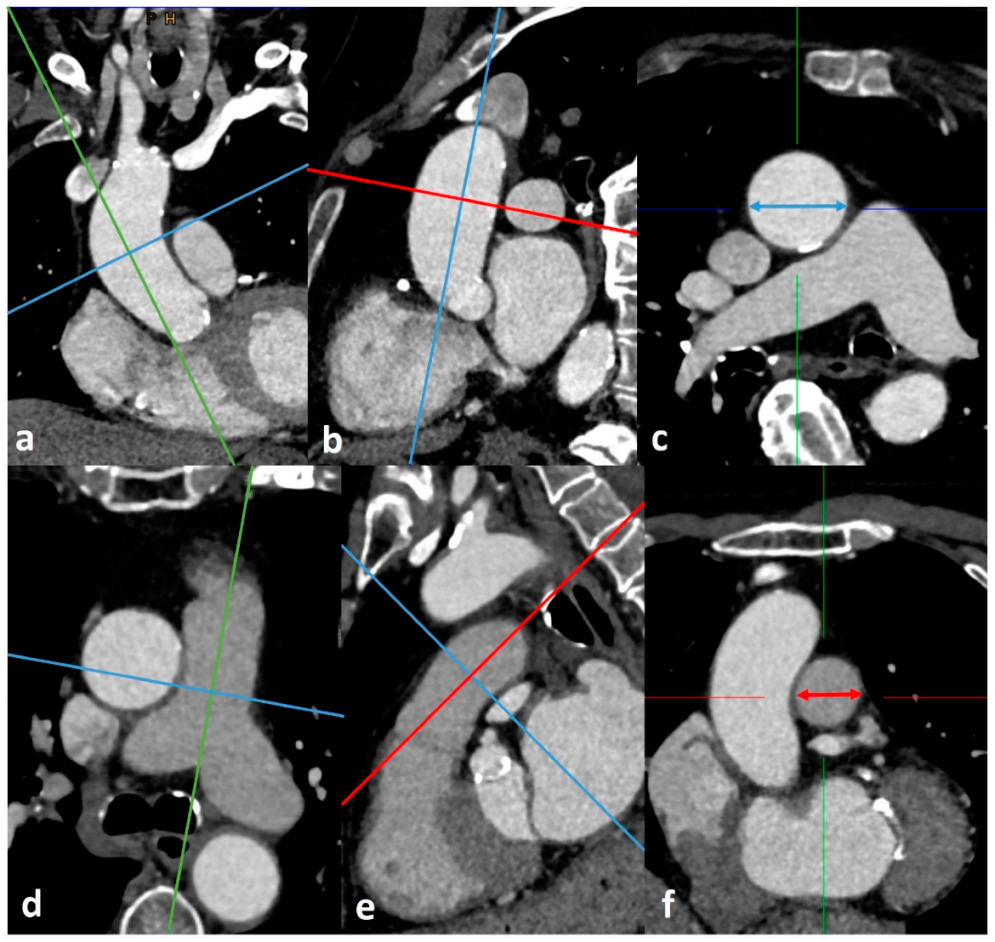

2.3. CTA Protocol and Measurement of Diameters for PH Assessment

- The widest short-axis diameter of the main pulmonary artery (PA) within 3 cm of the bifurcation of the pulmonary trunk.

- The widest short-axis diameter of the ascending aorta (AA) at the level of the bifurcation of the pulmonary trunk.

- The widest short-axis diameter of the right pulmonary artery (RPA).

- The widest short-axis diameter of the left pulmonary artery (LPA).